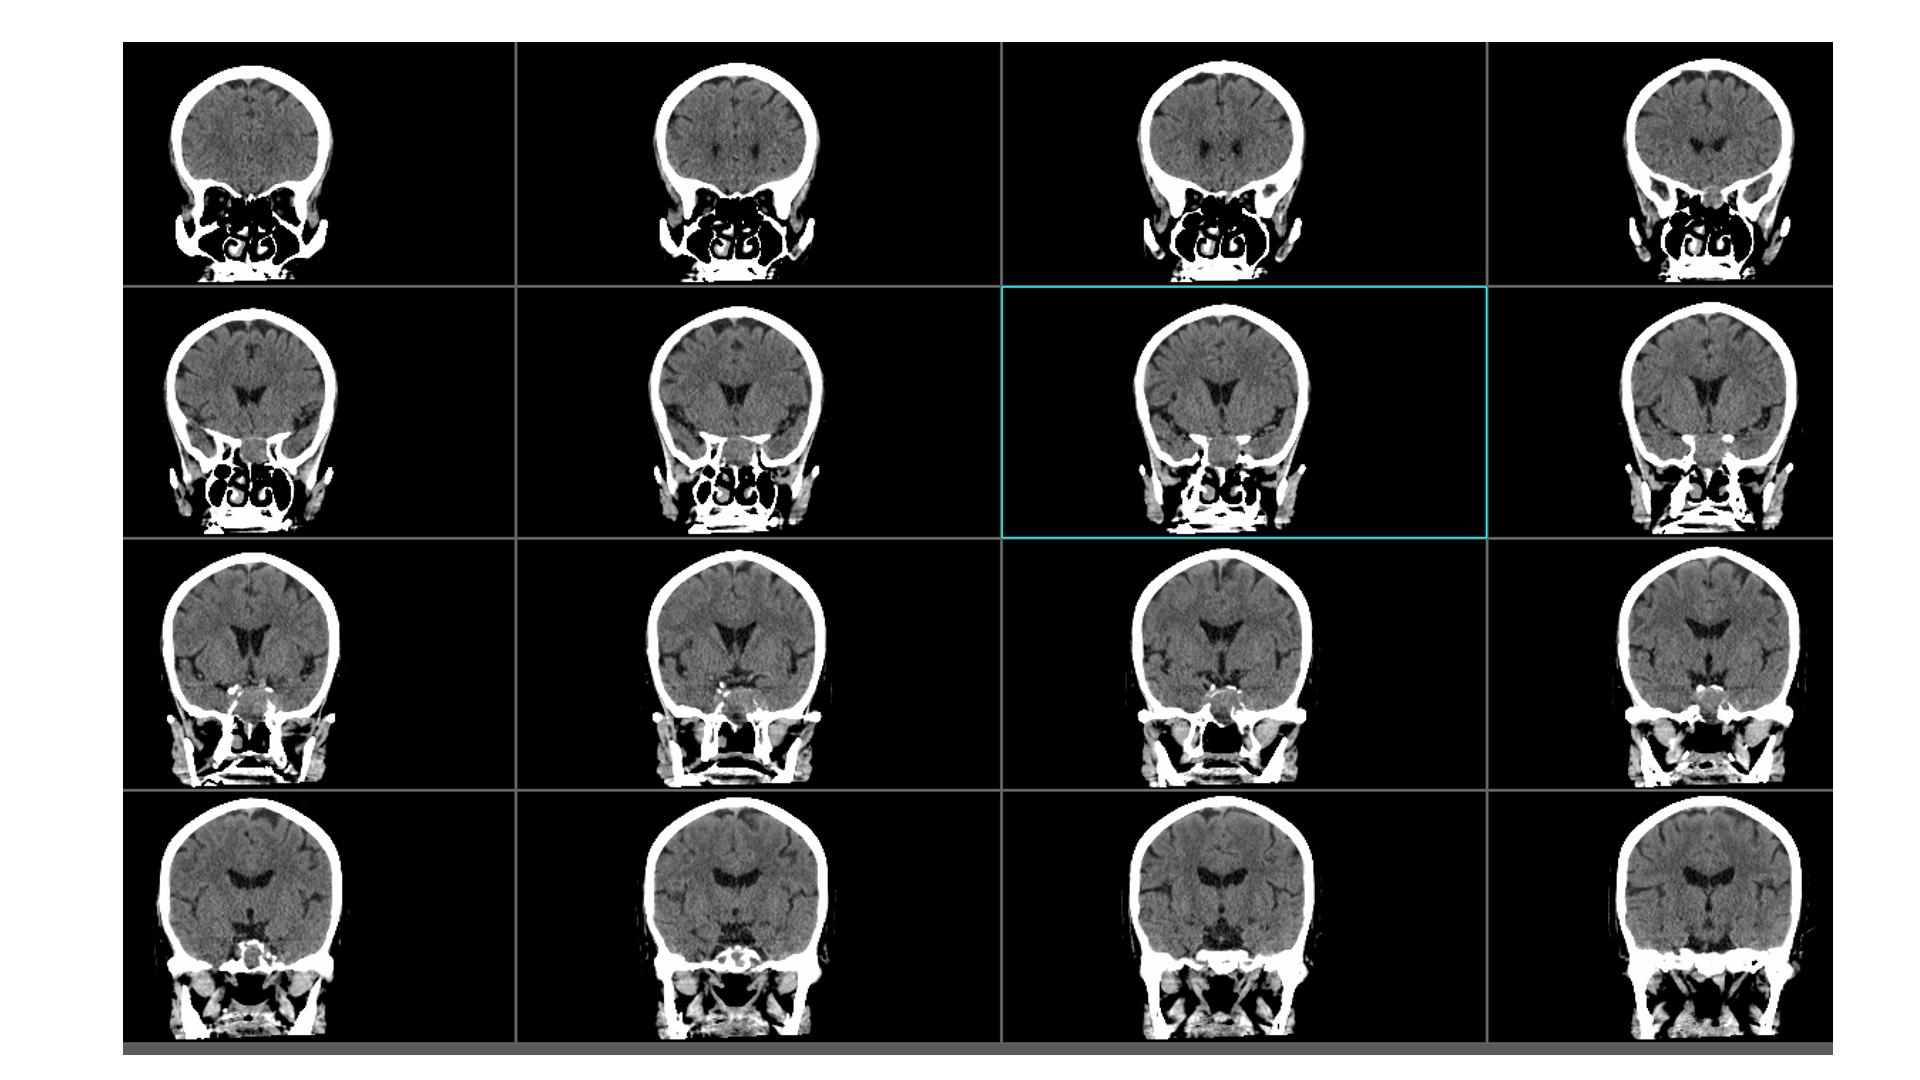

鞍区占位,蝶鞍扩大明显,侵袭海绵窦。